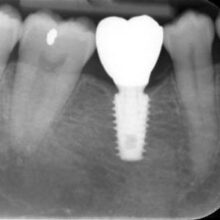

3. Final Restoration

Once healing is completed, a customised crown will be placed, which blends with the rest of your teeth, giving you back your ability to eat chew properly and making you feel more confident.